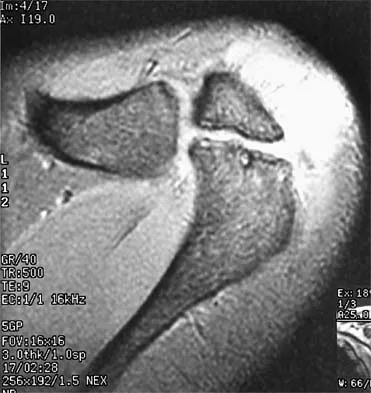

Figures 38a and 38b show the CT scans of a 64-year-old woman. What is the most likely diagnosis?

The CT scans show large cystic lesions in the talus and calcaneus with complete subluxation of the subtalar joint, allowing the calcaneus to slide laterally until it becomes blocked by the fibula. The cause of this subluxation is severe posterior tibial tendon dysfunction. Although no fibular fracture has yet appeared, it can occur with continued stress from the calcaneus. There is, however, a pathologic fracture in the medial calcaneus through a medial degenerative cyst. The joint space is irregular and not symmetrical as would be seen in an inflammatory arthropathy. Cystic lesions are not present in the tibia. No stress fracture is seen in the talus. Coughlin MJ: Sesamoids and accessory bones of the foot, in Coughlin MJ, Mann RA (eds): Surgery of the Foot and Ankle, ed 7. St Louis, MO, Mosby, 1999, pp 437-499.